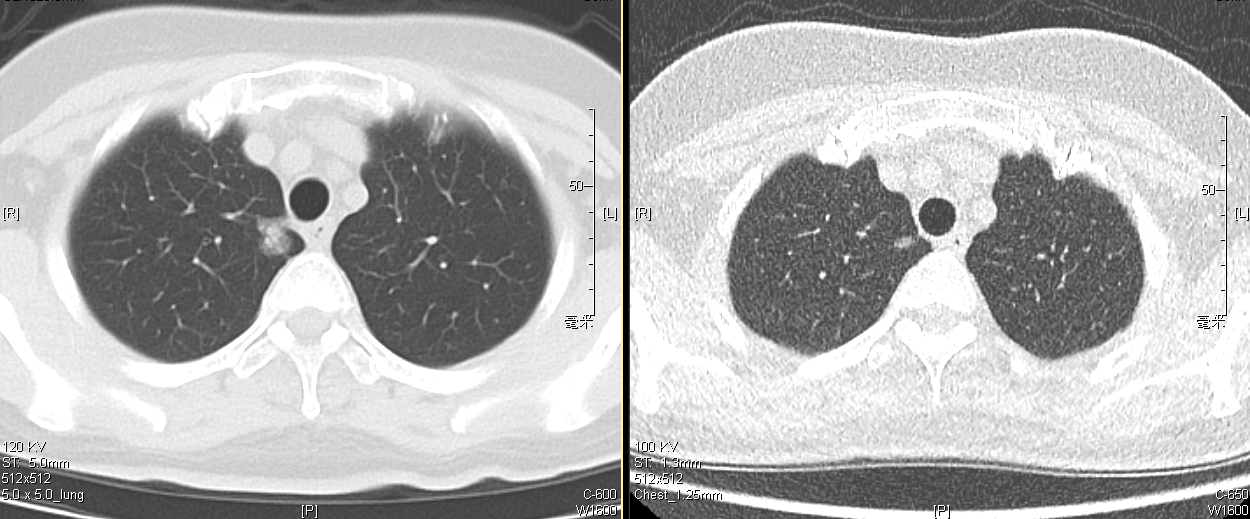

“主任,您快看看我的这个肺肿瘤,是不是没救了?如果做手术,能否尽可能微创?”2024年1月,满面愁容和焦虑的韩女士慕名来到北医三院胸外科强光亮主任的专家门诊。60岁的韩女士患有肺部结节5年,2周前复查胸部CT,发现了右肺上叶一个15mm的部分实性结节较前明显增大。

韩女士2024年(左)与2019年(右)胸部CT对比

“您放心,咱们可以尝试打1个孔,用手术机器人帮您根除它,这可能是最微创、最精准的办法。”强主任看完胸部CT后,和蔼地说道。经过了几周的观察,复查胸部CT排除炎症等疾病后,患者住进了北医三院胸外科的病房。